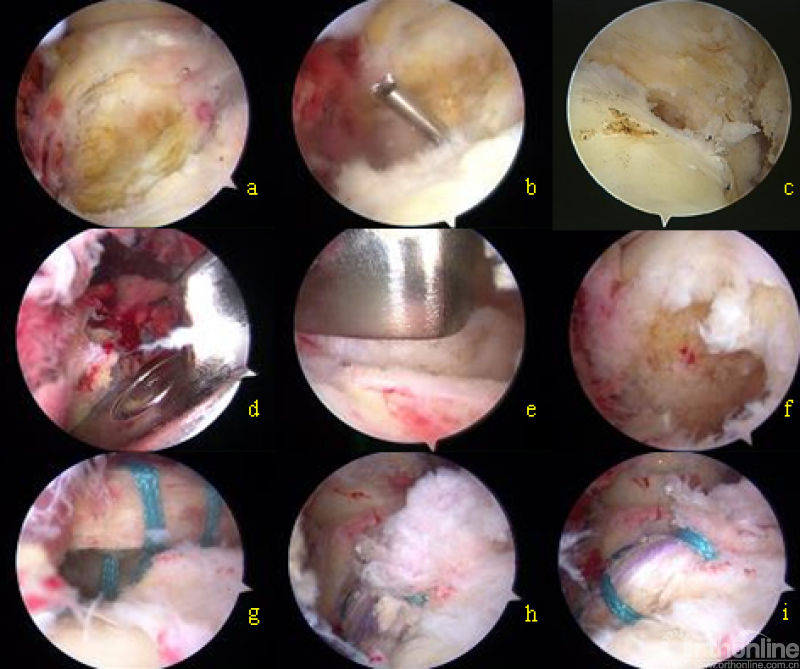

a 清理PCL胫骨止点;b 钻入定位针;c 导向孔;d 刀模和连接杆结合;e 刀模开槽;f 骨槽;g 引入移植物;h 骨块压配;i 固定后的状态